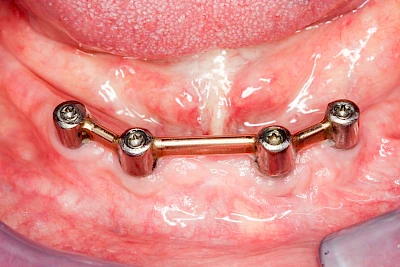

Implantate: Prothesen

Bei herausnehmbaren Prothesen werden Implantate eingesetzt, um den Halt und den Tragekomfort der Prothesen zu verbessern. Dazu kommen verschiedene Verbindungselemente zum Einsatz:

- Teleskope

- Kugelköpfe

- Tellerförmige Lokatoren

- Stege

- Magnete (selten)

Neben rein implantat-getragenen zahnärztlichen Versorgungen werden bei herausnehmbaren Prothesen Implantate auch in Sinne einer "strategischen Pfeilervermehrung" ergänzend zu eigenen Zähnen zur Verankerung eines Zahnersatzes genutzt.

Varianten zur Verankerung von abnehmbarem Zahnersatz auf Implantaten